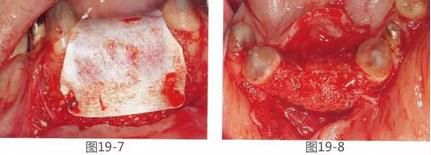

圖16-1,2  術(shù)前。有垂直以及水平牙槽嵴吸收。另外,左下2,3有深度牙周袋,附著齦也不足。